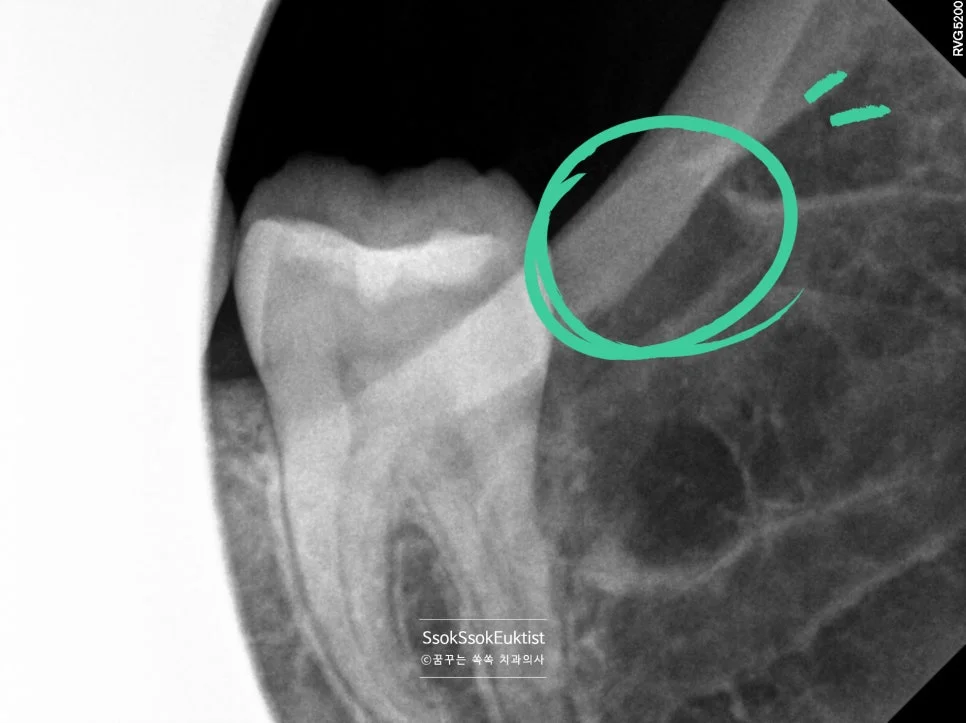

어려운 난이도 — 완전히 누워 있는 수평 매복 사랑니

X-ray 사진을 보면 사랑니가 완전히 누워 있어 사랑니를 빼기 위해서는 깊숙한 곳까지 도달하여 치아를 분리해야 할 것 같은데요~^^

CBCT 3차원 영상 — 서로 다른 방향으로 휘어진 복잡한 뿌리

3차원 사진을 통해 보면 뿌리가 서로 다른 방향으로 휘어 있어 뼈를 잡고 있는 모습인데요^^ 이런 뿌리의 사랑니의 경우 한꺼번에 나오지 않으므로 머리를 분리하는 것 외에 뿌리도 분리하여 사랑니를 제거해야 합니다.